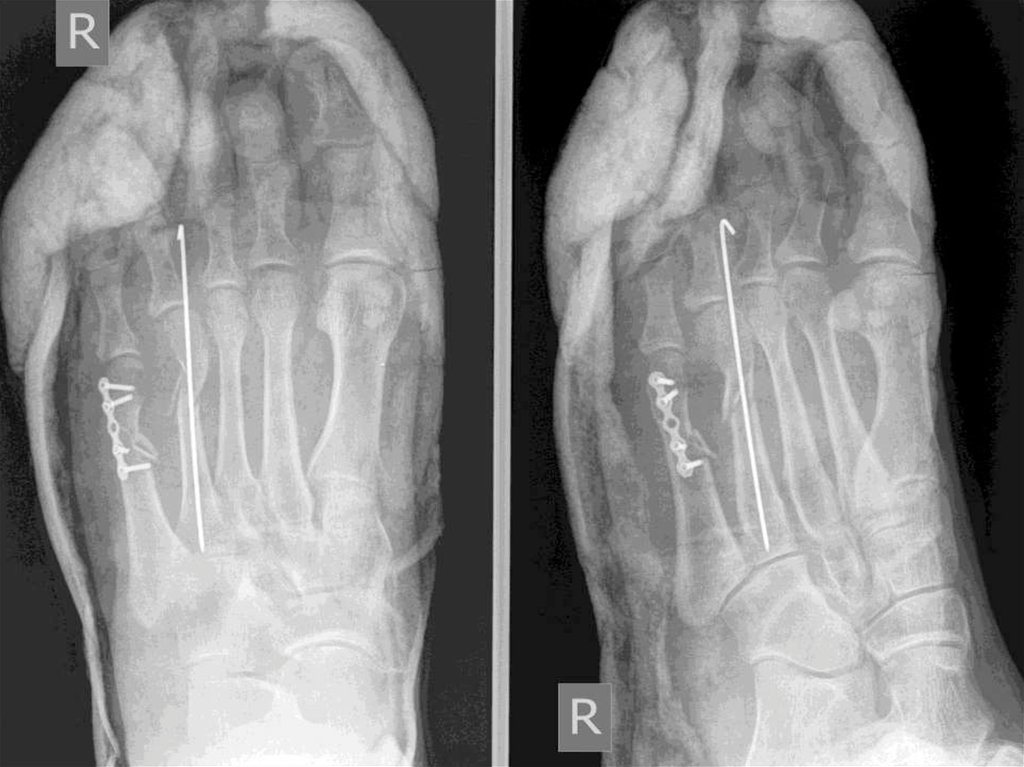

1.КУСАИНОВА ГУЛЬФИЯ 31.01.1990

(28жас)

Диагноз: IV, V оң табан сүйектерінің жабық

сынуы, ығысумен.

Операция: V табан сүйегінің ашық репозциясы,

остеосинтез пластинамен. IV табан сүйегінің

жабық репозицясы, остеосинтез спицамен.